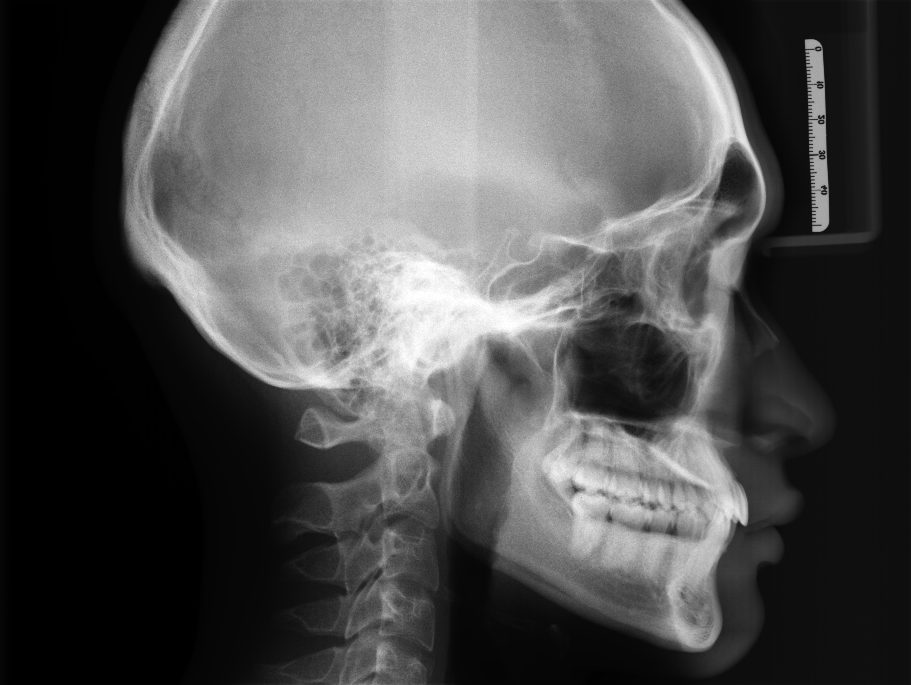

セファログラム(頭部X線規格写真)

安心して治療を始めるためには、レントゲン撮影(セファロ、パノラマ)や歯科用CTを用いた精密検査が重要です。

これらの検査によって、肉眼では見ることのできない歯根の長さや形、歯槽骨の量や質、顎の骨格などを三次元的に詳細に把握することができます。

当院ではセファロや歯科用CTを用いた精密な検査データに基づき、仮歯のある歯を動かしてもリスクがないかを正確に診断し、一人ひとりに合った安全な治療計画を立案します。